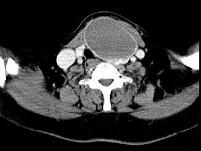

问题 女,56岁,发现颈部肿块1月余,CT如图所示,最可能诊断为()

选项 A.甲状舌管囊肿 B.甲状腺乳头状癌 C.甲状腺原发淋巴瘤 D.甲状腺腺瘤 E.甲状腺脓肿

答案 D